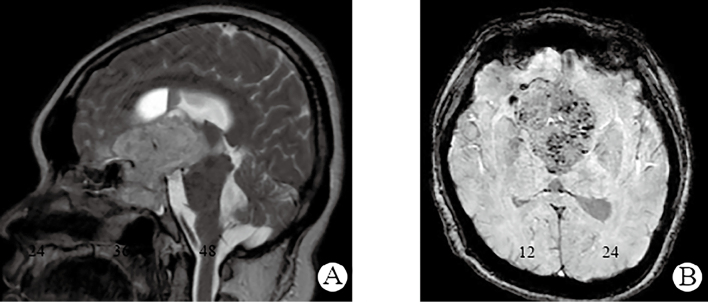

Successful Pregnancy in Woman With Hyperprolactinemia Associated With Hemorrhagic Giant Craniopharyngioma.